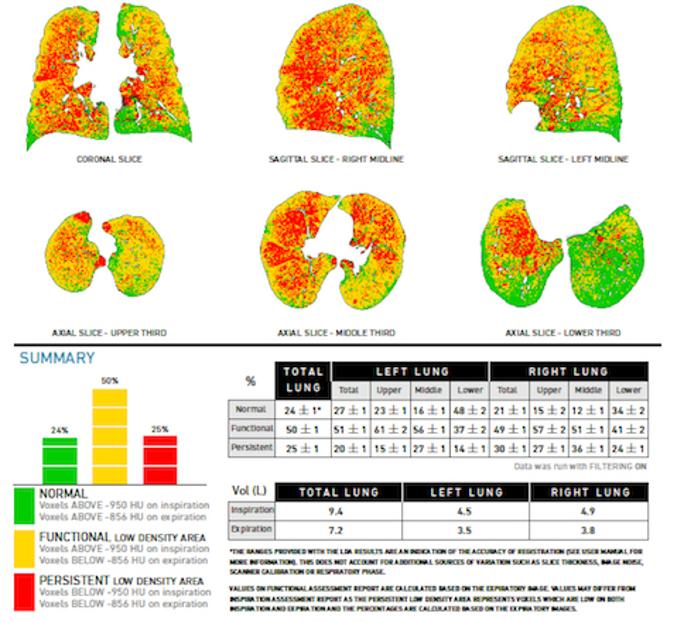

- Imaging animal models of pulmonary emphysema (in collaboration with the Horae Gene Therapy Center, UMass Chan Medical School)

- Functional imaging of large and small airways

- Imaging of COPD and smoking-related disease